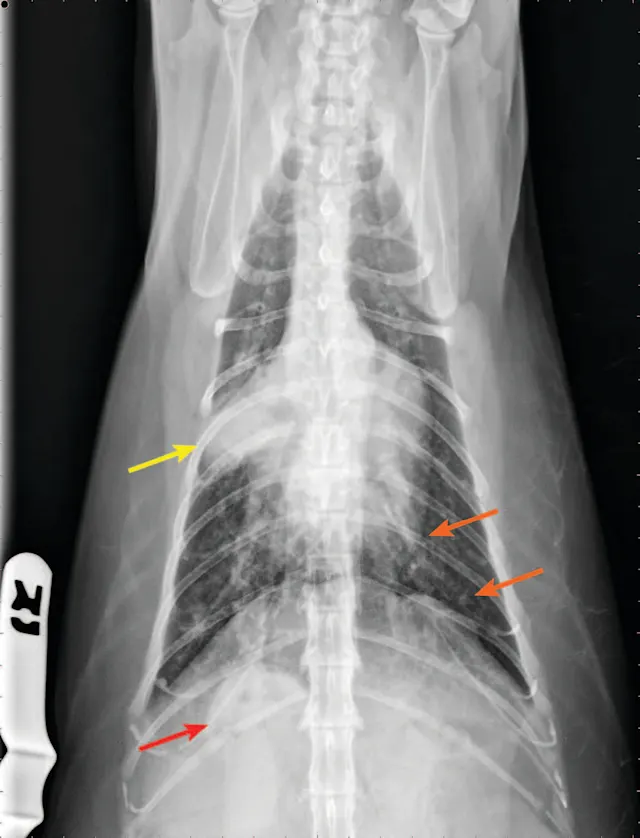

FIGURE 3

Radiograph of bronchopneumonia with more classic cranioventral distribution (arrows). Other diseases, including CHF, have a similar distribution. Lack of this pattern does not rule out infection.